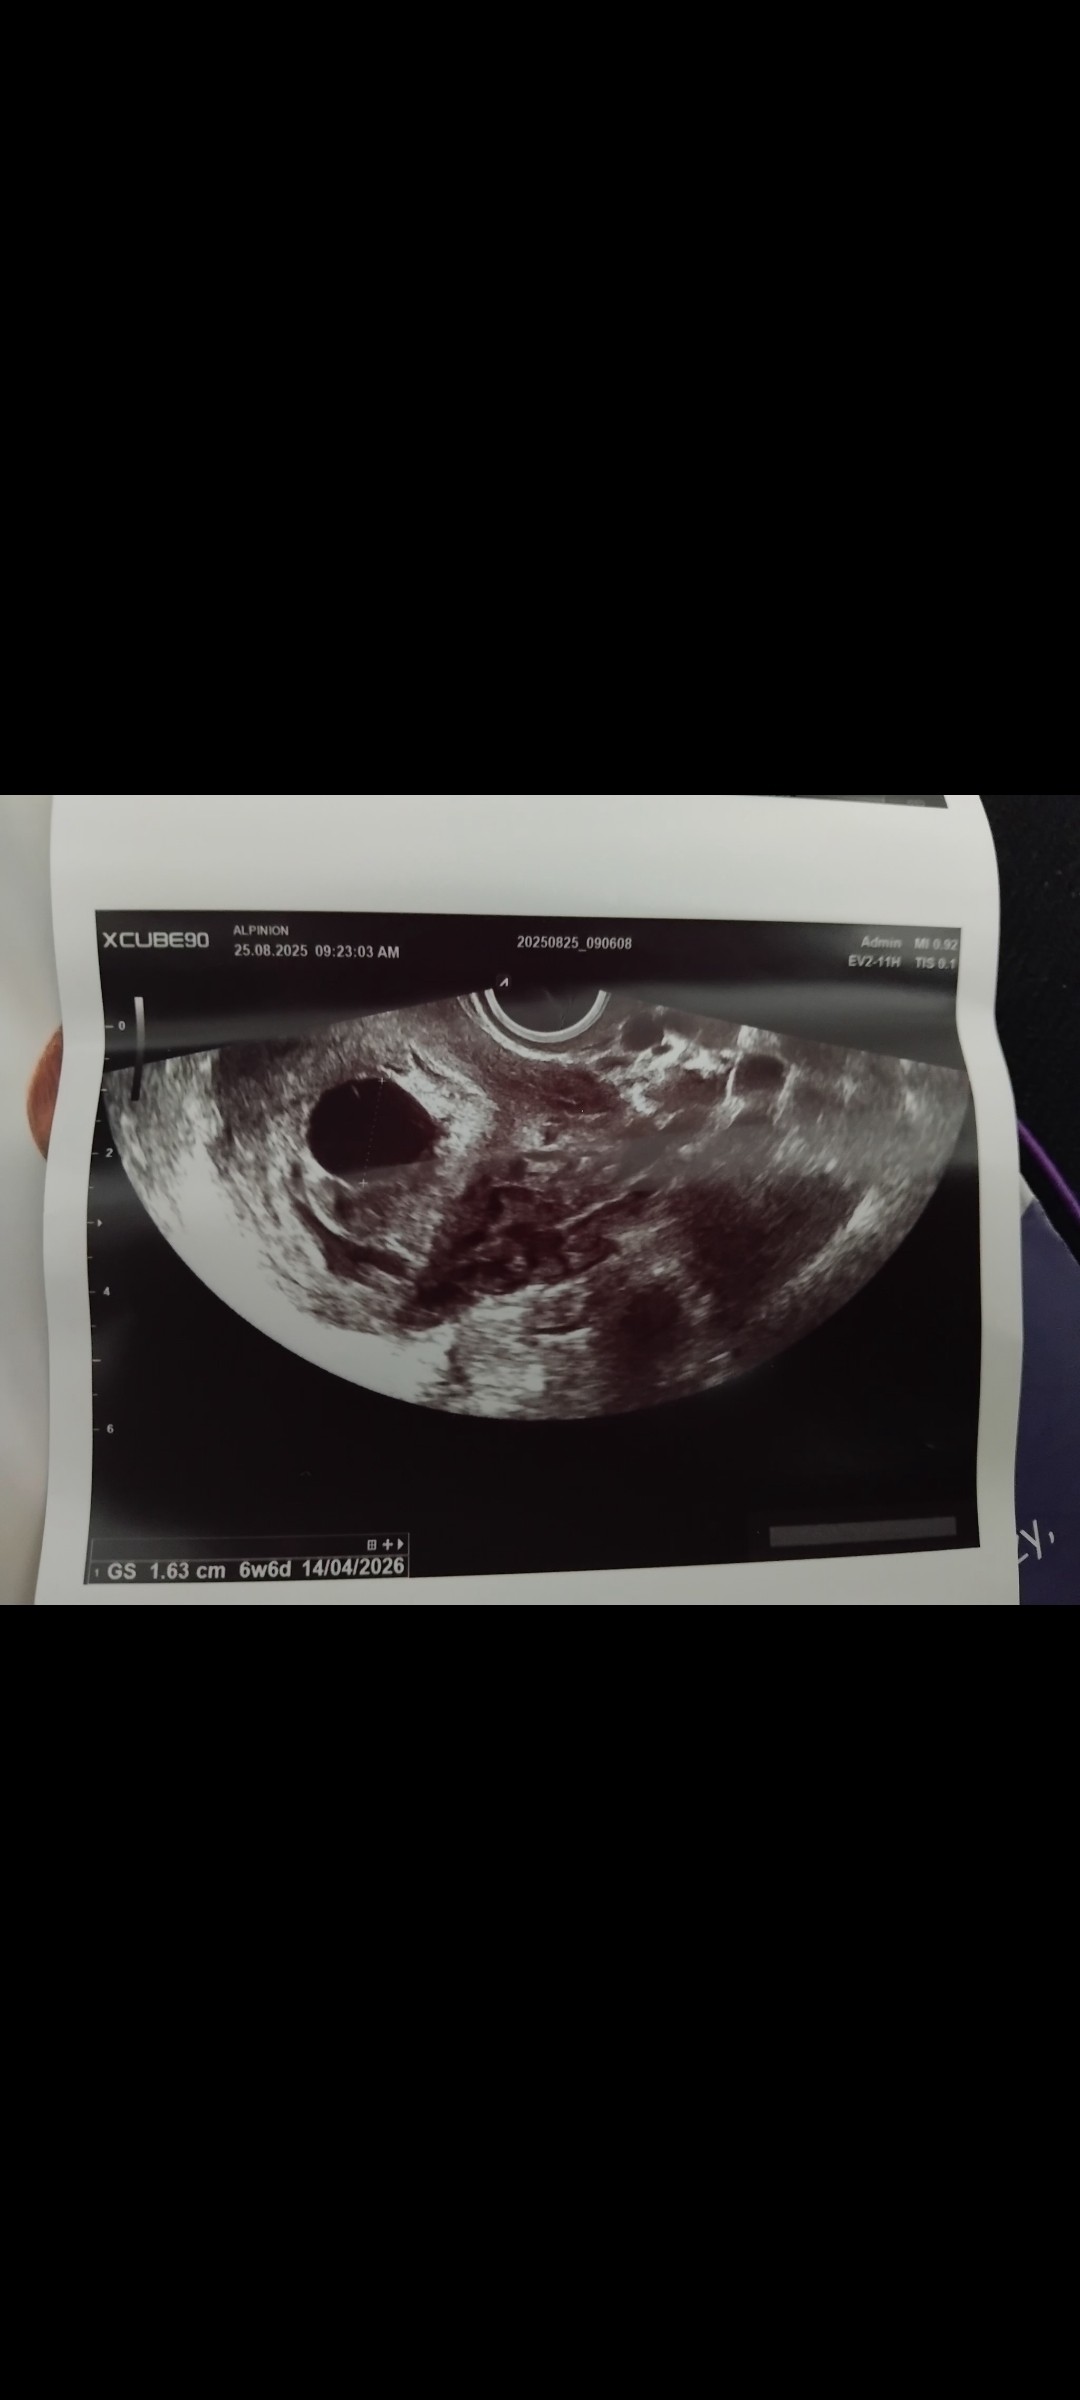

Dziś 25 sierpień kolejna wizyta pecherzyk ciążowy aktualnie ma 1.63 zarodka Dalej Brak

Mój pęcherzyk niby jest zbyt " okrągły" gdyby miał się pojawić zarodek robił by się bardziej owalny ...